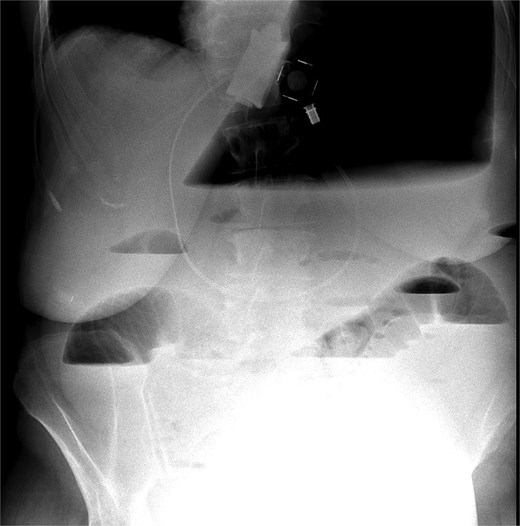

Immediate action involved removing fluid from the gastric band and inserting a nasogastric tube, which was slightly difficult. Only 200 ml of gastric content was drained, and no air was present (indicating that it was not in the stomach). Given the possibility of anatomical pathology or obstruction at the gastroesophageal junction (GEJ), we avoided excessive force when inserting the tube to prevent iatrogenic esophageal perforation. A computed tomography (CT) scan with liquid-soluble contrast media showed that the contrast did not pass beyond the band. The scan also revealed massive gastric dilatation, as well as dilation of the esophagus proximal to the band (Figs 2–4).

CT axial view—contrast media in distal esophagus did not pass to the stomach.